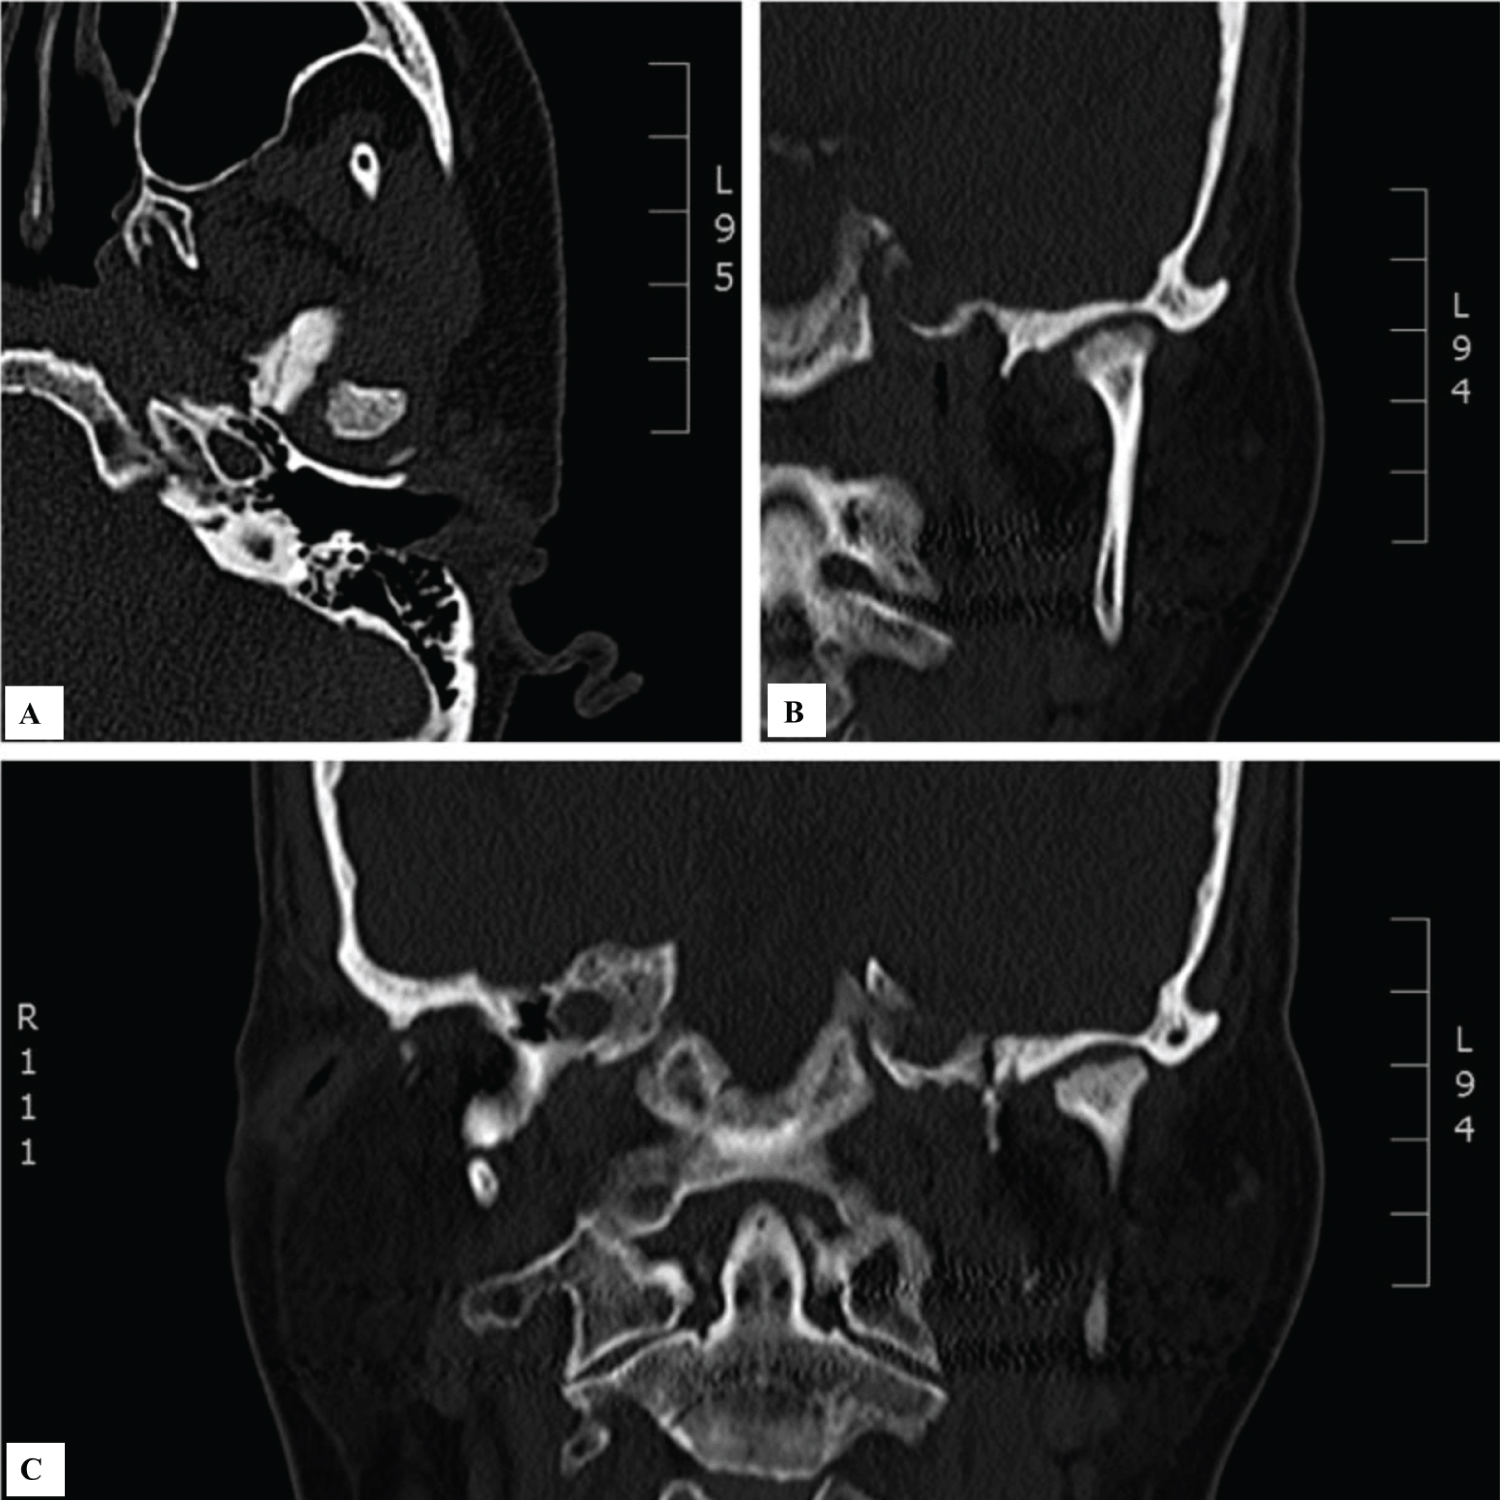

Intra-articular injection of Procenta can be effective in alleviating pain, restoring TMJ function and improving quality of life in patients with advanced degree of TMJ internal derangement. The regeneration of bone at the condylar head can potentially delay open joint procedures such as arthroplasty or total joint replacement for a prolonged period of time. Prospective randomized controlled trials are warranted to fully elucidate the efficacy and benefit of placental derived graft in treating TMJ disorders (Figure 3).

Figure 3: Preoperative computed tomography coronal image of a 31-year-old female patient with mild degenerative joint disease of bilateral temporomandibular joint (A) right TMJ complex; (B) left TMJ complex. Coronal view demonstrating regeneration of bone and well-defined cortical borders of the condylar head bilaterally 10 months postoperatively (C) right TMJ complex; (D) left TMJ complex. View Figure 3